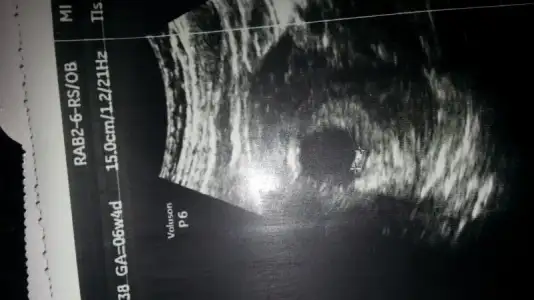

kızlar günaydın. benimkini de yorumlar mısnız? sat a göre 8+0 ama usg ye göre 8+5. teşekkürler şimdiden :) bu karından ultrason görüntüsü

Cnm ilk sayfada şöyle yazıyor;

Bu yöntem bircok kişide dogru sonuc verdii.

bebegin7-8 haftalıkkenki usg resimine direkt baktıgınızda;

bebek kesenin soluna yakınsa bebek erkek,

sagına yakınsa kız.

Senin bebek sola yakin,vajinal usg ile karından usg farklı.o yüzden seninki karındanmis bu teoriye erkek oluyor cnm.